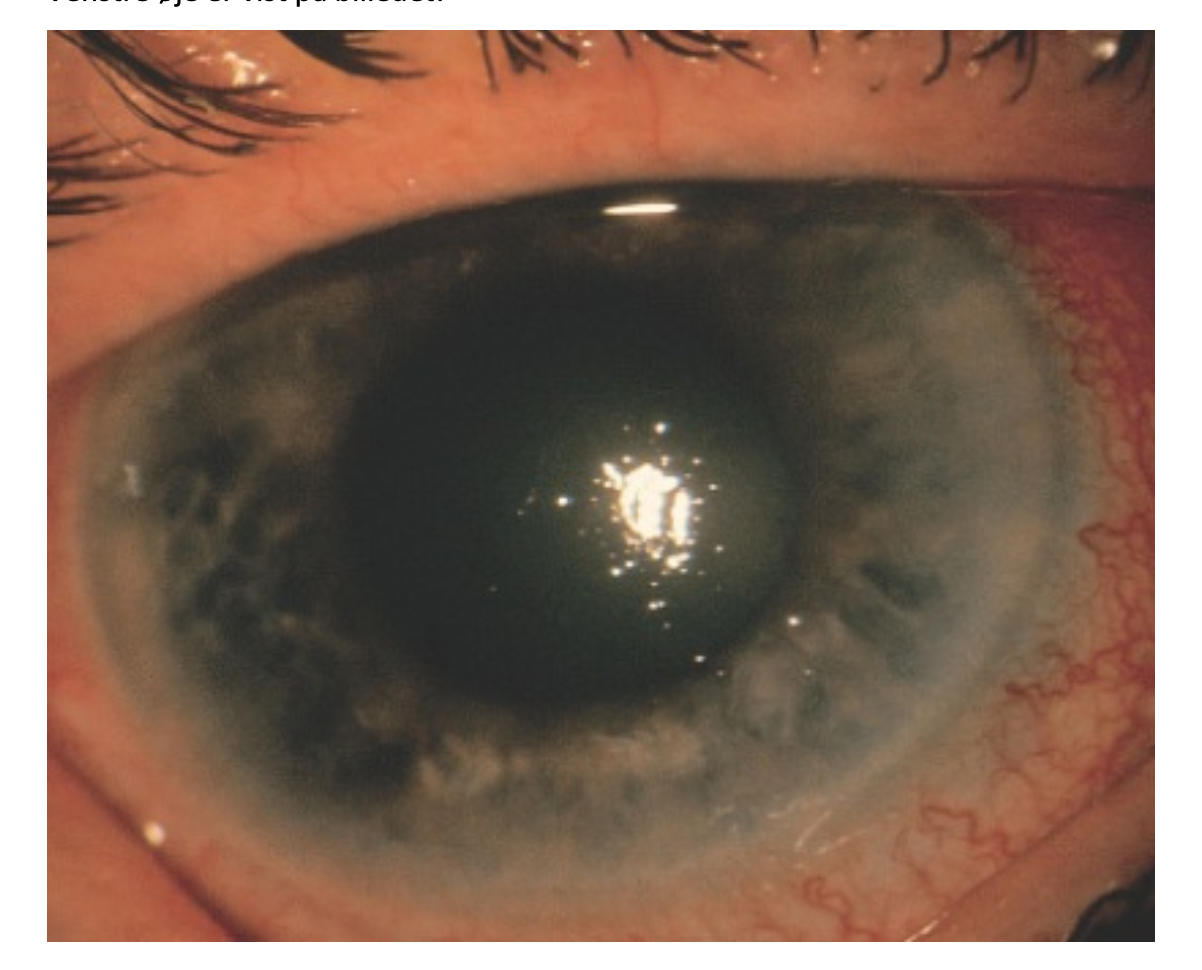

50 årig mand kommer til dig i skadestuen med pludseligt opståede stærke smerter svarende til

venstre øje. Smerterne har nu bredt sig til pande og tindingeregion. Han har gennem den seneste

måned oplevet 30 minutter lange, intermitterende smerter og regnbuesyn på venstre øje.

Er tidligere systemisk rask. Tager ingen medicin.

Er langsynet på begge øjne. Brilleglasmål: o.dxt. + 3 dioptrier, o.sin + 4 dioptrier.

Visus o.dxt. 1,0 (6/6). Visus o.sin. 0,25 (6/24)

Højre øje er blegt med klar cornea og lysreagerende pupil.

Venstre øje er vist på billedet:

Hvilken af følgende diagnoser er mest sandsynlig?

- Katarakt

- Iridocyclitis

- Bakteriel conjunktivitis

- Keratitis

- Akut glaukom

- Akut glaukom

Note:

Akut lukketvinklet glaukom er karakteriseret ved degeneration af synsnerven som følge af forhøjet intraokulært tryk forårsaget af vinklelukning.

Symptomer er:

- Øjensmerter

- Ciliær injektion

- Lysstiv middeldilateret pupil

- Cornea ødem (uklar cornea)

- Regnbuesyn

- Evt. kvalme og opkast

Den 50-årige mand har smerter i venstre øje, regnbuesyn, ciliær injektion og middeldilateret pupil ved lys.